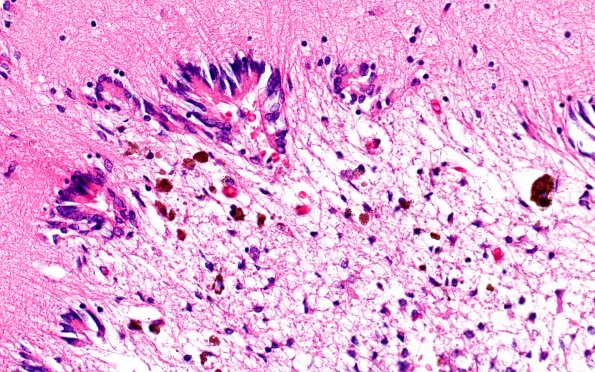

29B7 IVH (Case 29) N11 H&E 40X

The adjacent ependymal lining shows significant granular ependymitis. (H&E)